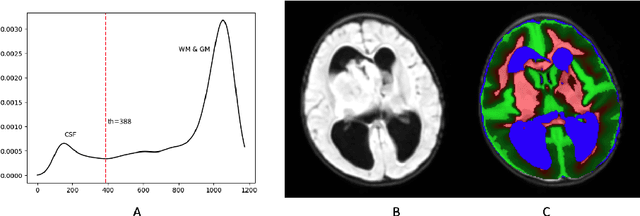

Abstract:In the past few years, deep learning (DL) models have drawn great attention and shown superior performance on brain tumor and subregion segmentation tasks. However, the success is limited to segmentation of adult gliomas, where sufficient data have been collected, manually labeled, and published for training DL models. It is still challenging to segment pediatric tumors, because the appearances are different from adult gliomas. Hence, directly applying a pretained DL model on pediatric data usually generates unacceptable results. Because pediatric data is very limited, both labeled and unlabeled, we present a brain tumor segmentation model that is based on knowledge rather than learning from data. We also provide segmentation of more subregions for super heterogeneous tumor like atypical teratoid rhabdoid tumor (ATRT). Our proposed approach showed superior performance on both whole tumor and subregion segmentation tasks to DL based models on our pediatric data when training data is not available for transfer learning.